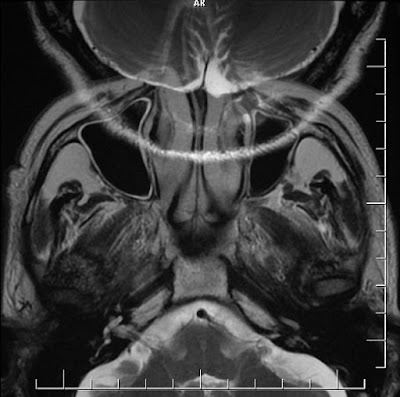

यह artifact water and fat के interphase के कारण होता है क्योंकि processing

के दौरान proton हर जगह एक समान signal नही देता है जिसके कारण misreadingहोती है और यह artifact image से कुछ जगह dark और कुछ जगह light spotका निर्माण करती है और image को नुकसान पहुंचता है यह artifact generally abdomen and स्पाइन और orbit के border में दिखाई देता है इस artifact को कम करने के लिए fat saturated sequance को run करना चाहिए।